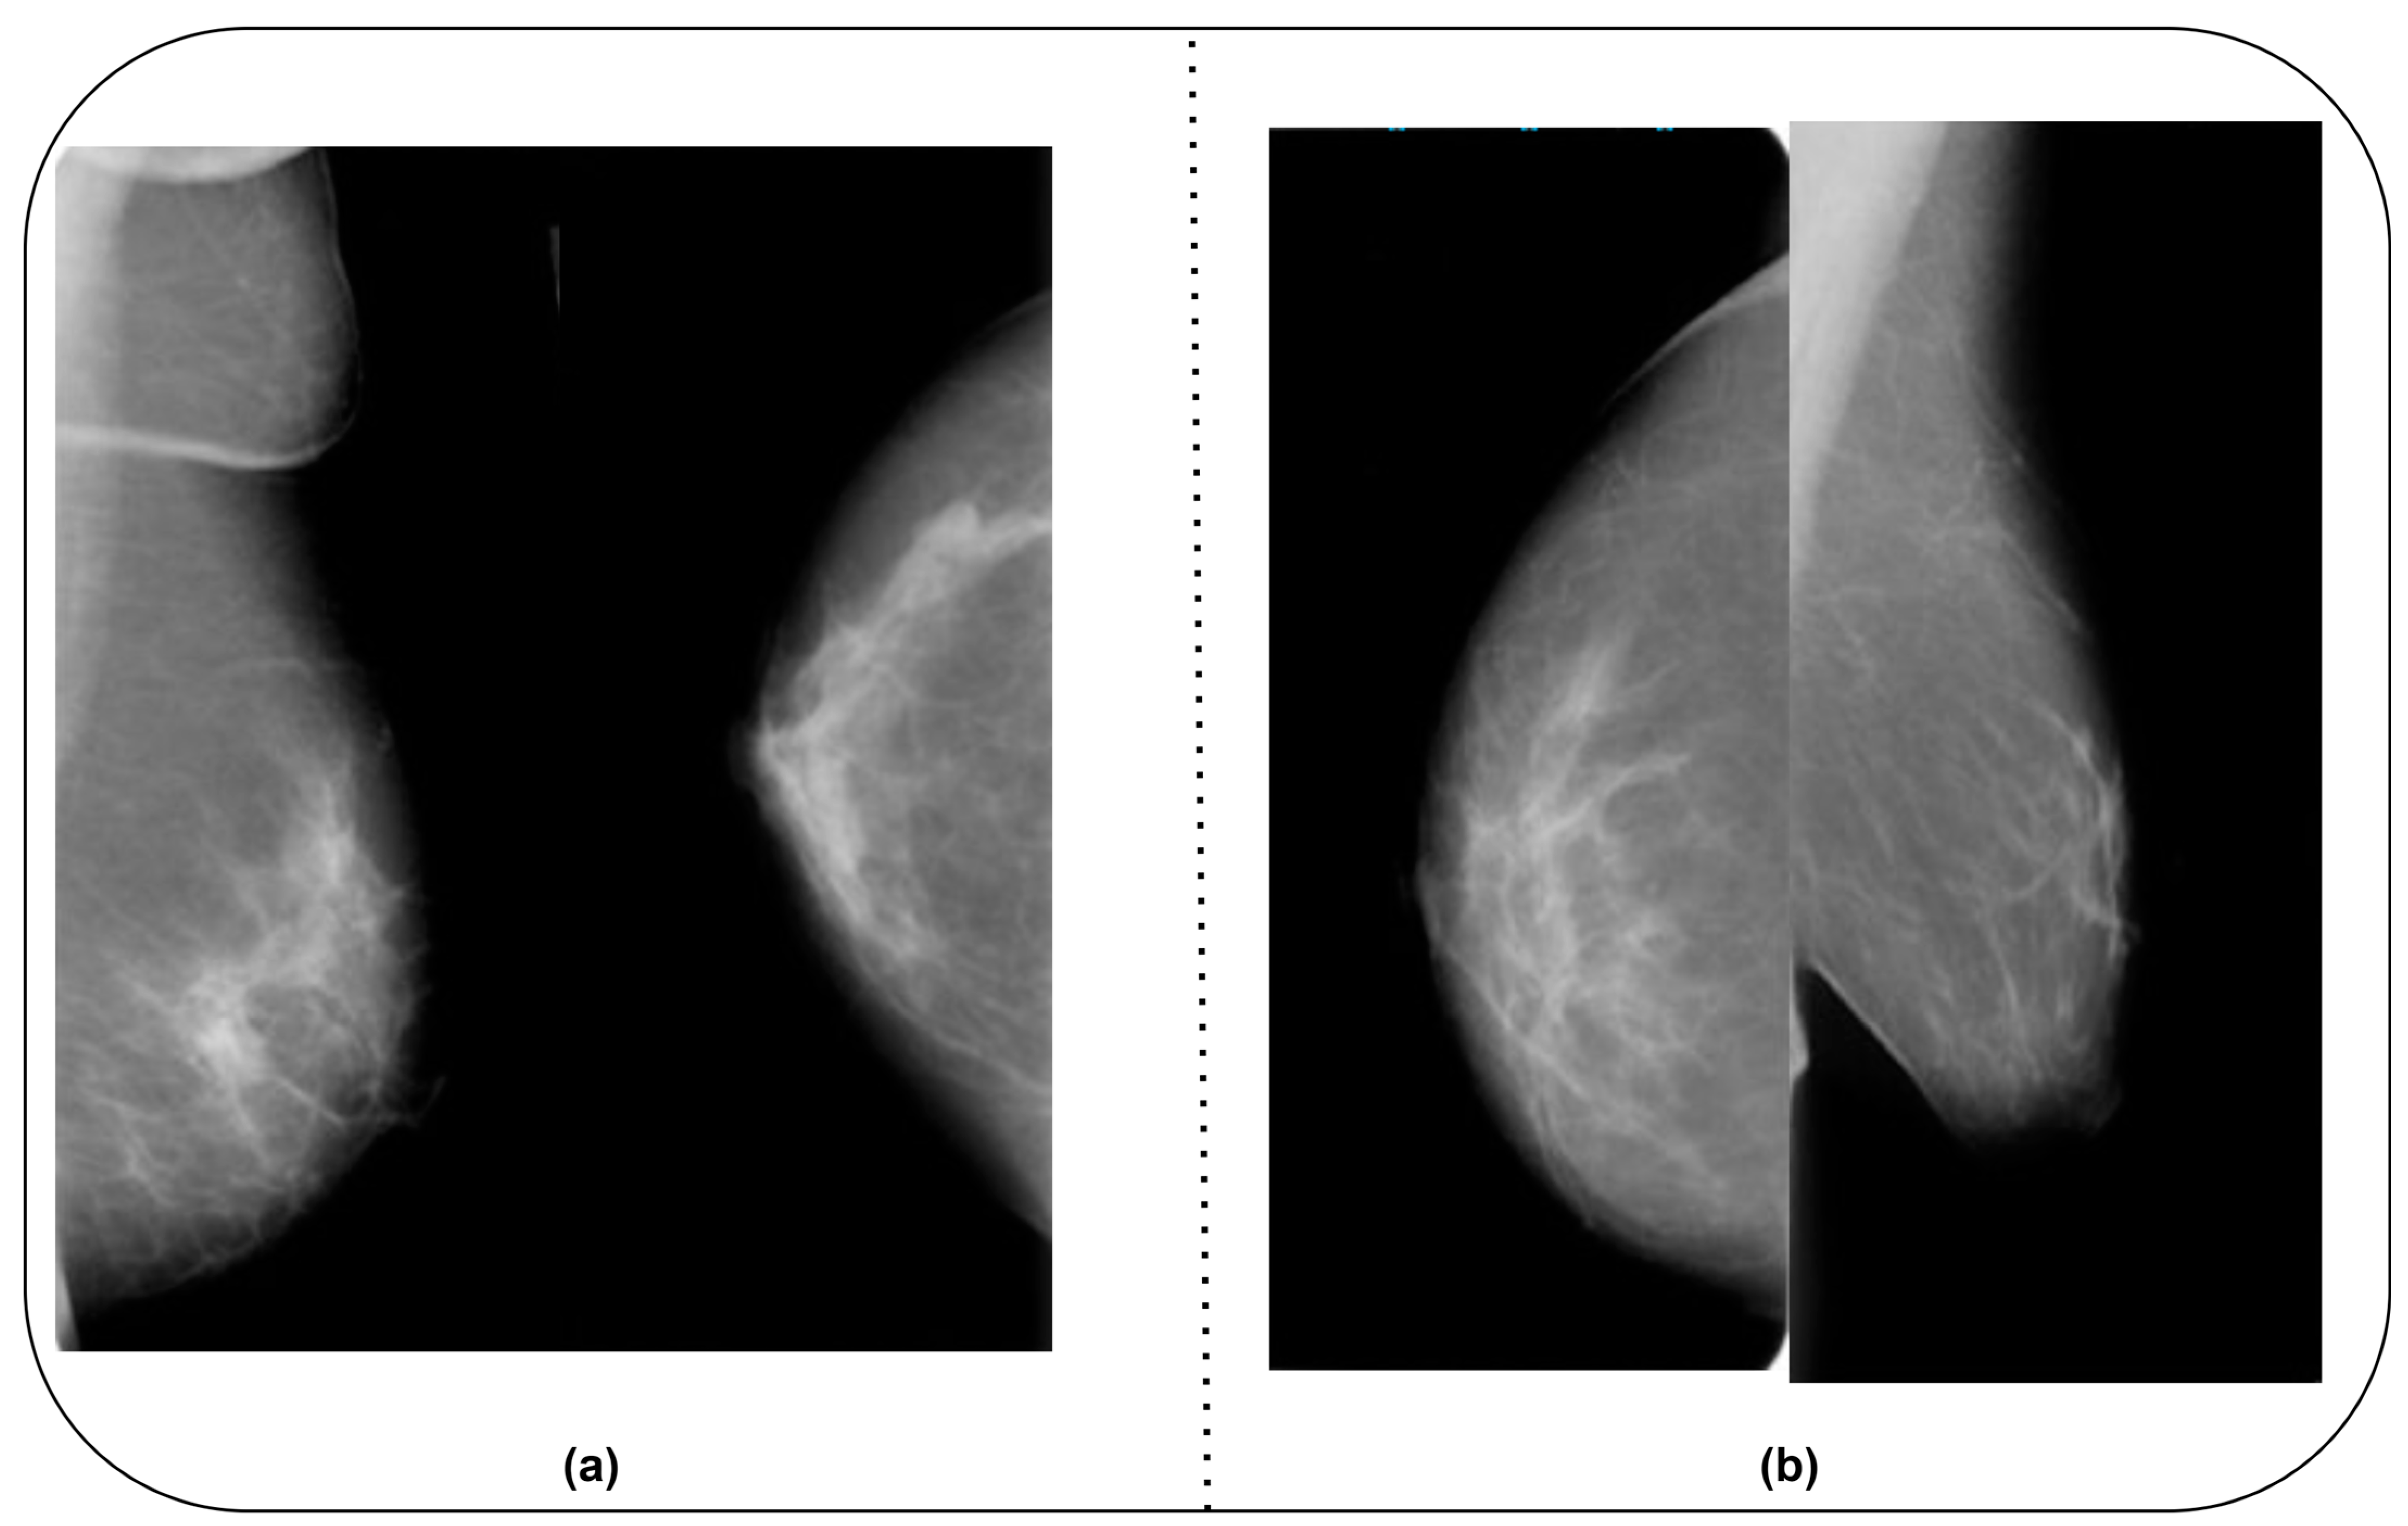

The CMMD dataset includes two datasets. CMMD1 encompasses mammography and clinical data, whereas CMMD2 covers malignant BC images. The dataset owner obtained the images from Sun-Yat-Sen University Cancer Center in Guangzhou and Nanhai Affiliated Hospital of Southern Medical University, Guangdong, China. The data were collected between July 2012 and July 2016. To ensure the efficiency of the proposed BC detection model and to use a unique dataset, the authors combined the CBIS-DDSM and CMMD datasets. They included benign and malignant images from the MIAS [28] and BCDR-D [29] datasets. Table 1 highlights the details of the datasets. Figure 2a,b show sample images from the CBIS-DDSM and CMMD datasets.

Figure 2. (a) CBIS-DDSM dataset. (b) CMMD dataset.